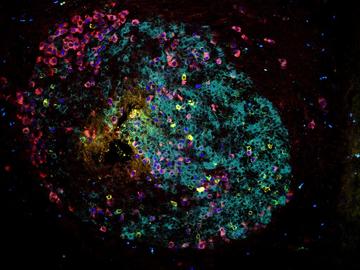

Striking Laboratory Data Images

Laboratory Data Gallery

Universe of the brain